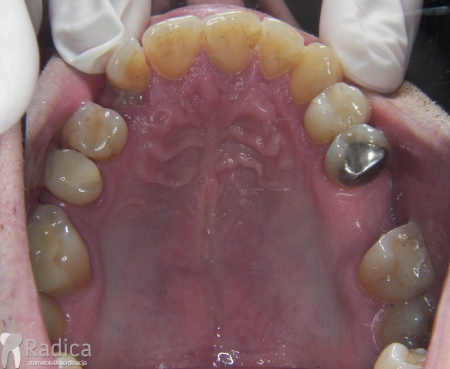

U galeriji slika su prikazani klinički slučajevi ovakvih odraslih pacijenta bilo da se radi samo o ortodontskoj terapiji ili predprotetskoj ortodonciji.

U sljedećem primjeru je fiksna ortodontska terapija rađena samo u donjoj čeljusti. Nakon toga su napravljeni novi protetski radovi u gornjoj i donjoj čeljusti – rad dr. Gorana Radice.

Na sljedećoj slici se mogu vidjeti početak i kraj ortodontske i protetske terapije. Protetske radove radio je dr. Goran Radica.